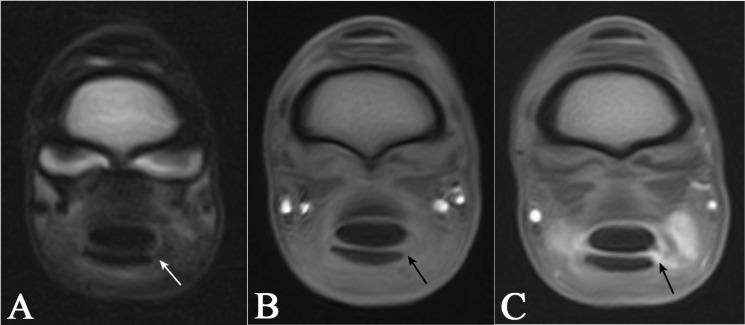

Diagnosing digital flexor tendon sheath (DFTS) pathologies, particularly manica flexoria (MF) tears, can be challenging with standard imaging modalities. Standing low-field MRI tenography (MRIt) may improve the detection rate of MF tears. This study aimed to compare ultrasonography, contrast radiography, pre-contrast MRI, and MRIt to detect naturally occurring MF lesions in horses undergoing tenoscopy. Ten horses with a positive DFTS block, which underwent contrast radiography, ultrasonography, MRI, MRIt, and tenoscopy were included. Two radiologists evaluated the images and recorded whether an MF lesion was present and determined the lesion side. Sensitivity and specificity were calculated for each modality using tenoscopy as a reference. MRIt and contrast radiography detected MF lesions with the same frequency, both showing 71% sensitivity and 100% specificity. Pre-contrast MRI and ultrasonography detected MF lesions with a lower sensitivity (57%); however, the MRI (100%) demonstrated a higher specificity than ultrasonography (33%). Adding contrast in MRI changed the sensitivity from (4/7 lesions) 57% to (5/7 lesions) 71%, with a constant high specificity (100%). MRIt diagnoses MF tears with a similar sensitivity to contrast radiography, with the same specificity, but with the added benefit of lesion laterality detection. The combined advantages of the anatomical detail of the T1 sequence and the post-contrast hyperintense appearance of the fluid may help diagnose MF tears and identify intact MFs. However, this needs to be substantiated in a larger number of cases.

摘要

诊断指屈肌腱鞘(DFTS)病变,尤其是屈肌总腱鞘(MF)撕裂,采用标准成像方式具有挑战性。站立位低场MRI肌腱造影(MRIt)可能提高MF撕裂的检出率。本研究旨在比较超声检查、造影X线摄影、造影前MRI和MRIt,以检测接受关节镜检查的马匹中自然发生的MF病变。纳入10匹DFTS阻滞阳性且接受了造影X线摄影、超声检查、MRI、MRIt和关节镜检查的马匹。两名放射科医生评估图像,记录是否存在MF病变并确定病变侧。以关节镜检查为参考,计算每种检查方式的敏感性和特异性。MRIt和造影X线摄影检测到MF病变的频率相同,敏感性均为71%,特异性均为100%。造影前MRI和超声检查检测MF病变的敏感性较低(57%);然而,MRI(100%)的特异性高于超声检查(33%)。MRI中添加造影剂后,敏感性从(4/7个病变)57%变为(5/7个病变)71%,特异性保持较高(100%)。MRIt诊断MF撕裂的敏感性与造影X线摄影相似,特异性相同,但还具有检测病变侧别的额外优势。T1序列的解剖细节和造影后液体的高信号表现相结合的优势,可能有助于诊断MF撕裂并识别完整的MF。然而,这需要在更多病例中得到证实。